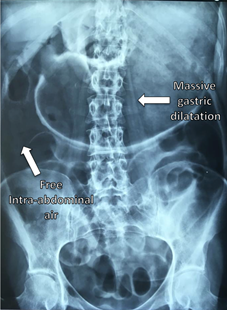

Laboratory tests showed: Hemoglobin: 13.2g/dl, Hematocrit: 41.3%, Leucocytes: 7.8103/L, Bands: 2%, Platelet: 353103/L, BUN: 14.2mg/dl, Creatinine: 0.83mg/dl, Na: 12meq, K: 3.80meq, Cl: 108meq, Ca: 6.60meq, P: 3.29meq, Albumin: 4g/dl, AST: 23U/L, ALT: 12U/L, Alkaline phosphatase: 91U/L, LDH: 244U/L, Amylase: 265U/L, Lipase: 11U/L. Plain abdominal and chest X-rays showed acute gastric dilatation and massive pneumoperitoneum (Figures 1&2). Due to the medical and surgical history which included chronic use of NSAIDs, as well as her symptoms, physical exam and imaging studies, the suggestive diagnosis of hollow viscus perforation was made, so an exploratory laparoscopy was performed to address the problem. Laparoscopic inspection of the abdominal cavity, revealed free serous fluid in the pelvic cavity without evidence of sepsis or intestinal fluid (Figure 3). A dilated stomach without obvious perforation and gas infiltration in lesser omentum was observed (Figures 4&5). An exhaustive review was carried out throughout the small bowel from Treitz ligament to the ileocecal valve and the entire colon length to rule out possible sites of perforation, without finding any evidence of it. Aspiration of the liquid and thorough irrigation of the abdominal cavity with saline solution was performed, and finally drainage was placed in the subhepatic space. Postoperative course was uneventful. She was started on liquids at 48hs after surgery, the drainage was removed and she was discharged on the fifth day after the surgical procedure. She was seen at the office several times after this event. Currently she lives a normal life, without restrictions secondary to this episode.

Figure 1 Massive gastric dilatation and free intra-abdominal air.

Figure 2 Bilateral free subdiaphragmatic air.